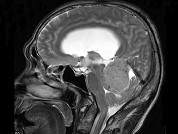

单项选择题男,61岁, 头晕头痛伴行走不稳1月余,请根据所提供图像, 选择最可能的诊断是 ( )

A、淋巴瘤

B、转移瘤

C、胶质瘤

D、髓母细胞瘤

E、(天幕切迹缘)脑膜瘤